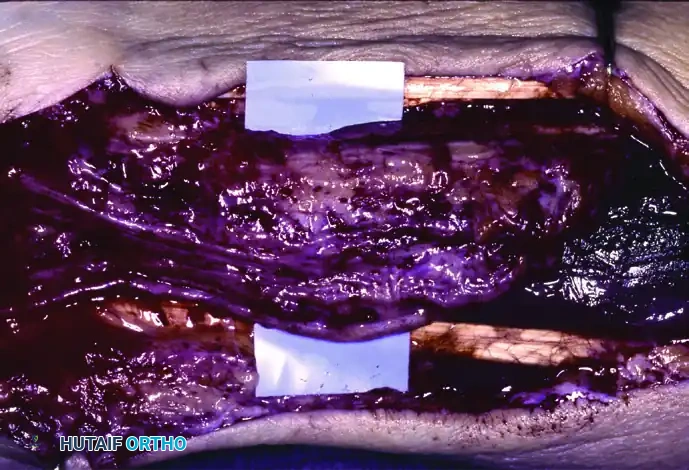

Extensive involvement of the median nerve coursing from the distal third of the forearm into the palm, demonstrating massive fibrofatty hypertrophy.

A closer intraoperative view of severe enlargement of the median nerve. Note the loss of normal fascicular architecture due to infiltration.